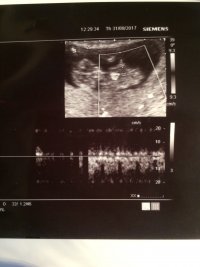

Bu iki fotoyada yorum alabilirmiyim bir arkadaşımın bebeği çok merak ediyor yüklememi istedi

Merhaba, görselde nub çıkıntısı görülmüyor. Ayrıca bu haftalarda cinsiyet tahmini hekimlerin çoğu yapmaz çünkü yanıltıcı olabilir. Bebeğinizin cinsiyetini net olarak 20. haftadan itibaren öğrenebilirsiniz.